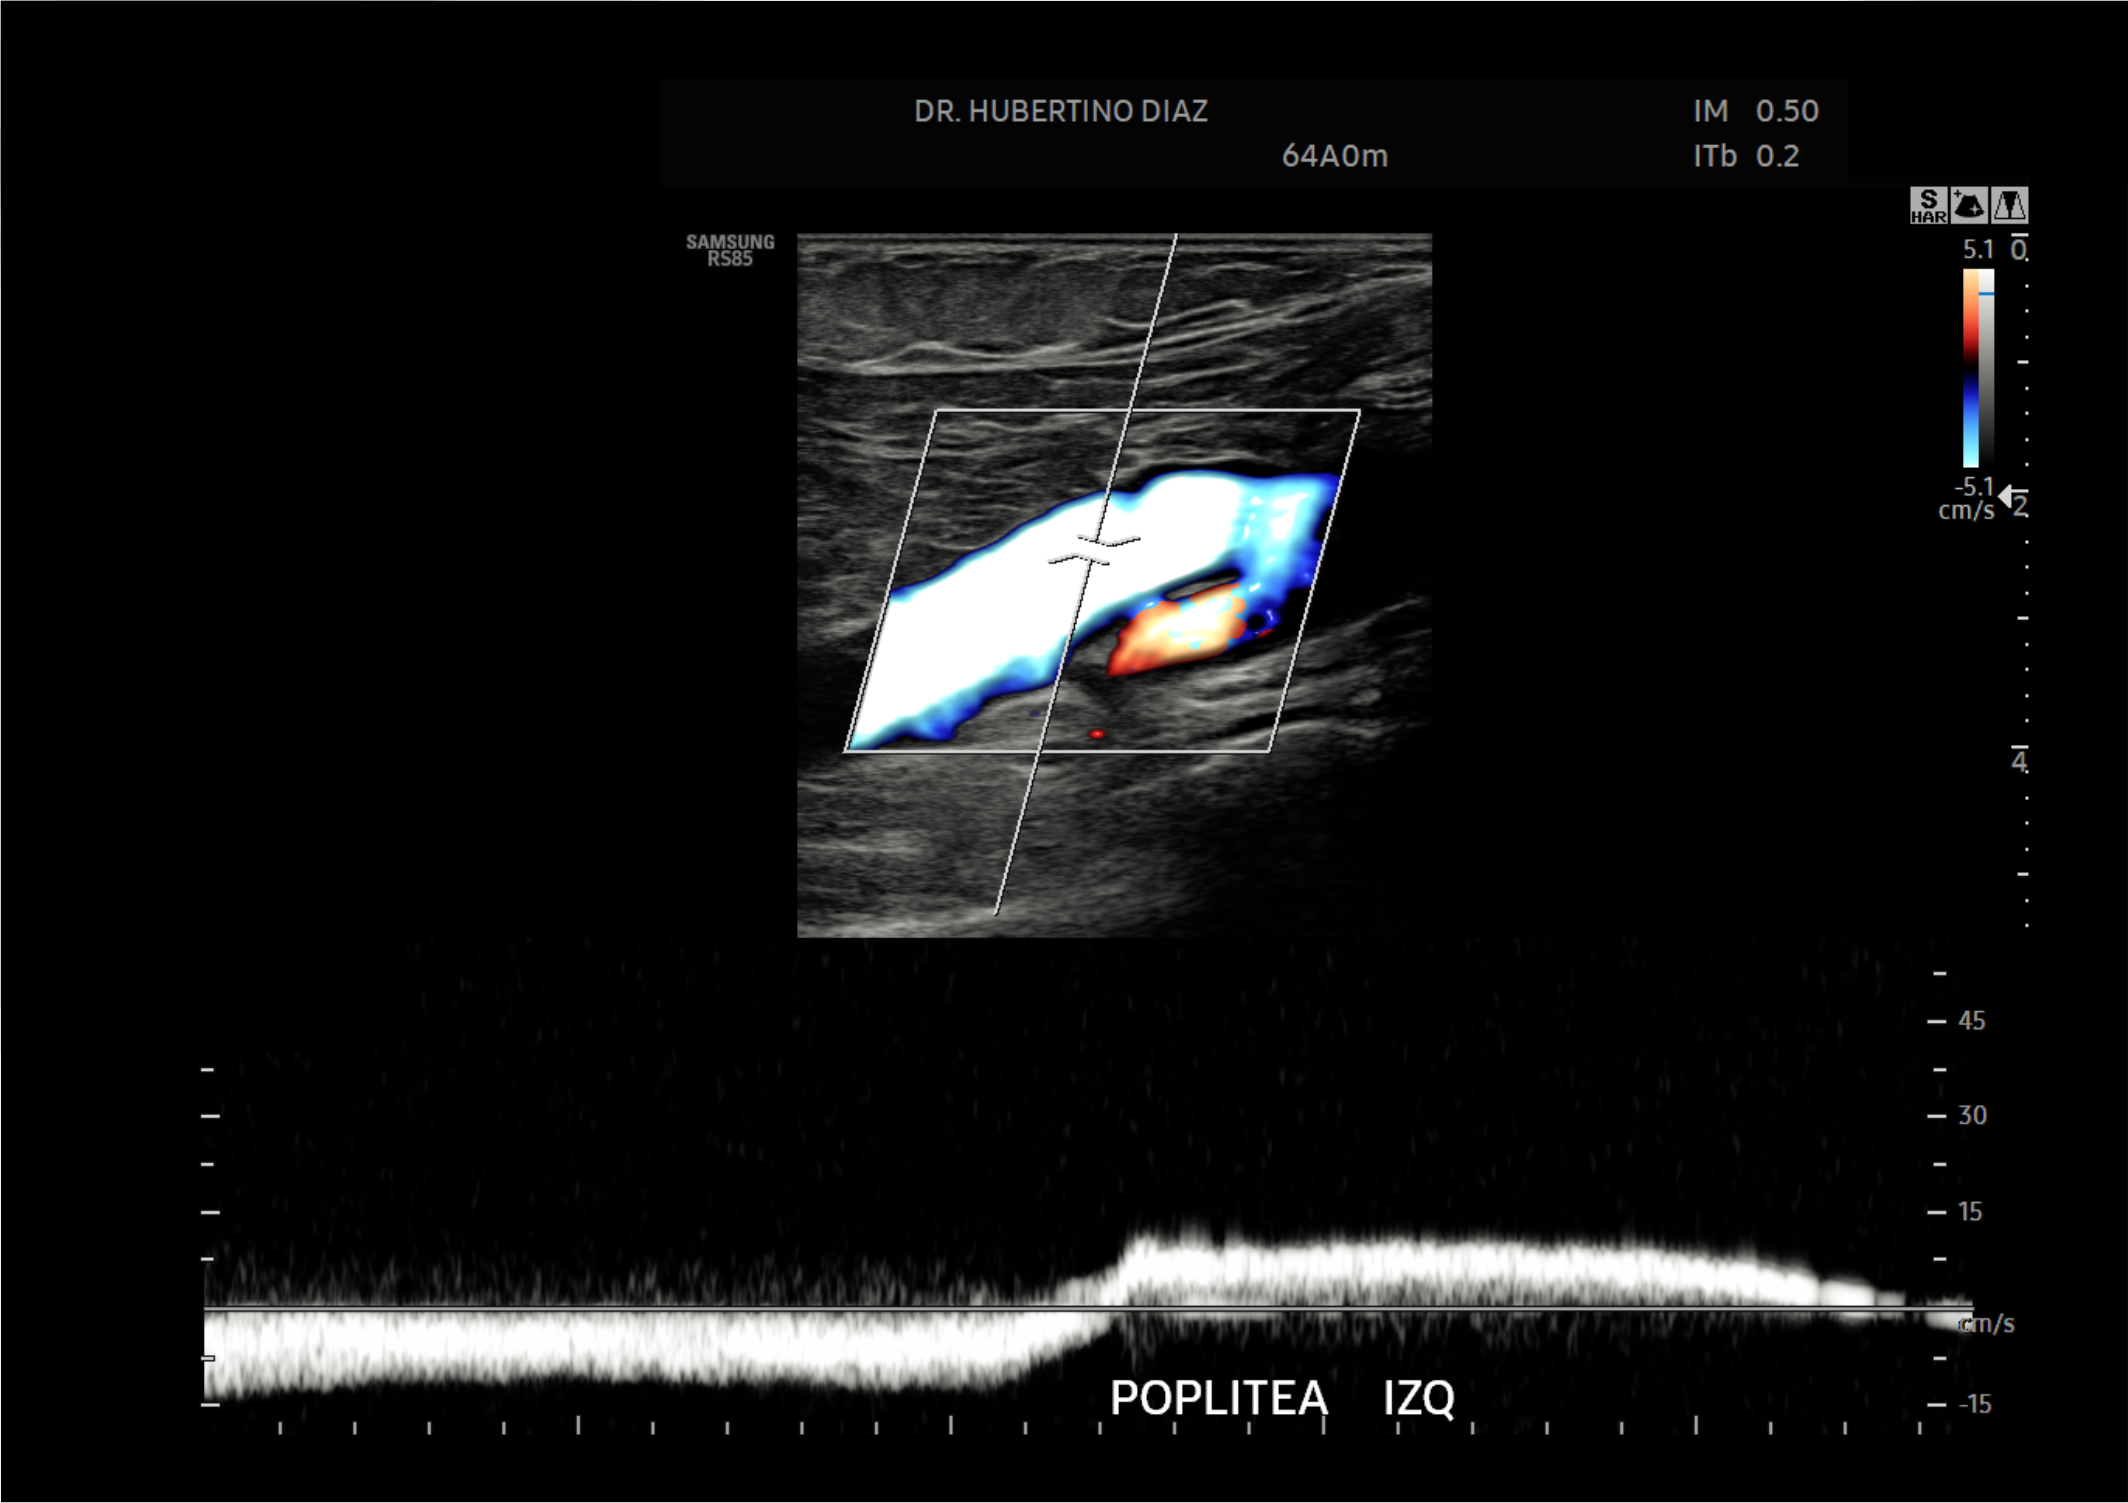

En Diagnoimagen incorporamos un enfoque de ecografía multiparamétrica, combinando modo B, Doppler color, Doppler de microflujo y elastografía, lo que nos permite una evaluación más completa y precisa en múltiples patologías.

🔹La ecografía Doppler permite evaluar el flujo sanguíneo en arterias y venas, siendo fundamental para el diagnóstico de insuficiencia venosa, várices, trombosis, estenosis carotídea y patología hepática.